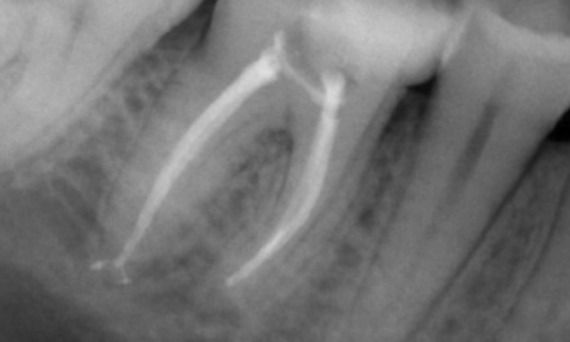

Before: Periapical radiolucency associated primarily with the distal root and loss of lamina dura on the mesial root.

After: TruNatomy was chosen in this case to allow a caries leveraged approach and a focus on pericervical dentin preservation especially on the mesial aspect where the tooth had a more minimal restoration.

Bath, UK